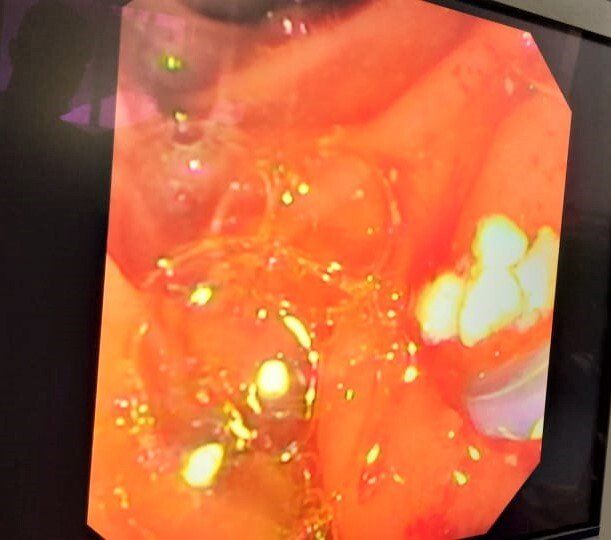

A Challenging Scenario: 40-year-old male with idiopathic chronic pancreatitis with intractable pain and sitophobia